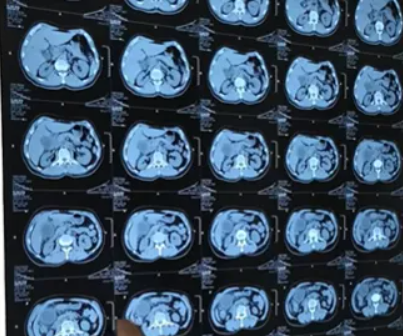

他是一名企业销售因常年酒局应酬,查出胆囊结石后放任不管,近日凌晨突发腹痛、黄疸、高烧,确诊胆囊结石急性发作伴严重并发症,万幸来我院就诊及时才得以缓解。

我院双镜联合微创术

功能保留:双镜配合,取石彻底,保留胆囊功能微创快速:腹部仅几厘米小孔,出血少、疼痛轻安全低复发:操作精准,并发症少、复发率低适用广:单发、多发结石均可考虑(需胆囊功能良好)